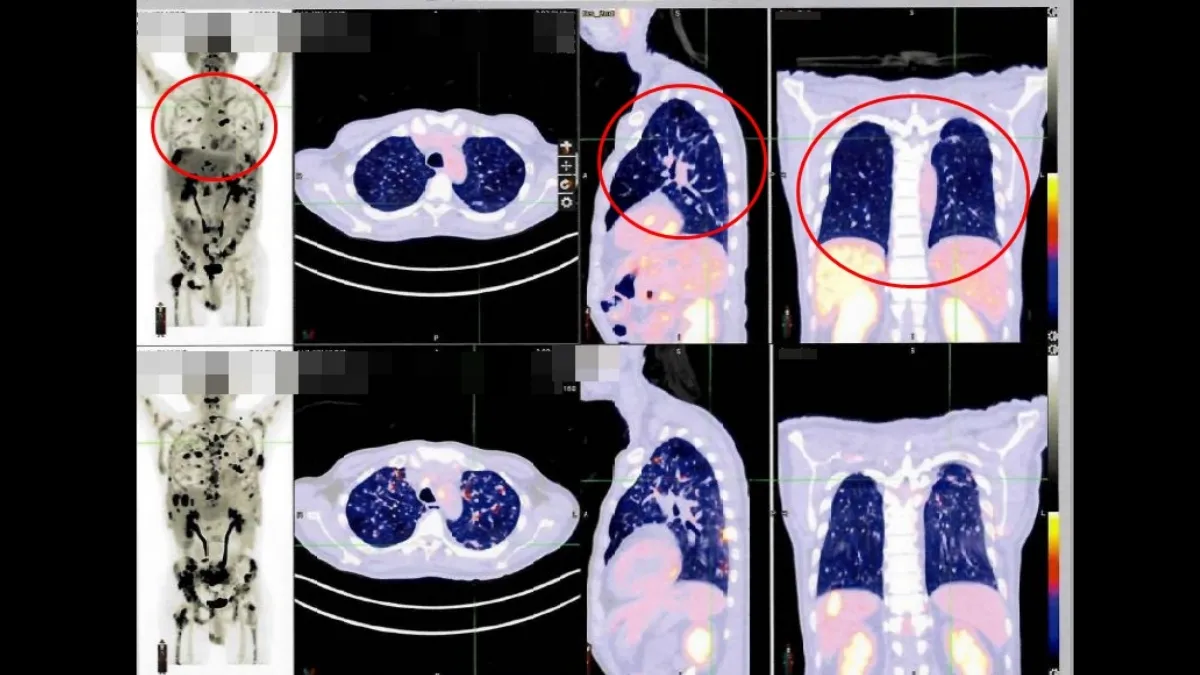

連嗎啡都壓不住!肺癌骨轉移讓他絕望 跨海來台做「這治療」終於能睡好覺

...疫藥物治療。然而,效果卻不如預期,疾病控制不佳所衍生出的劇烈骨痛,讓他即便服用高劑量止痛藥,仍無法有效緩解。 長期且劇烈的疼...